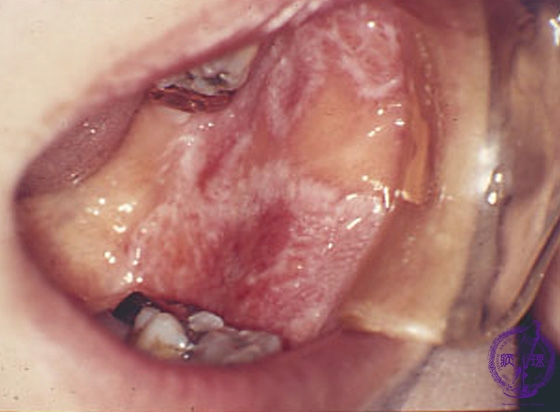

Macroscopic finding:Intraoral photograph. A white reticular (lace-like) lesion with erosive reddish area (arrow) in the buccal mucosa.

Click the image to see the enlarged image.